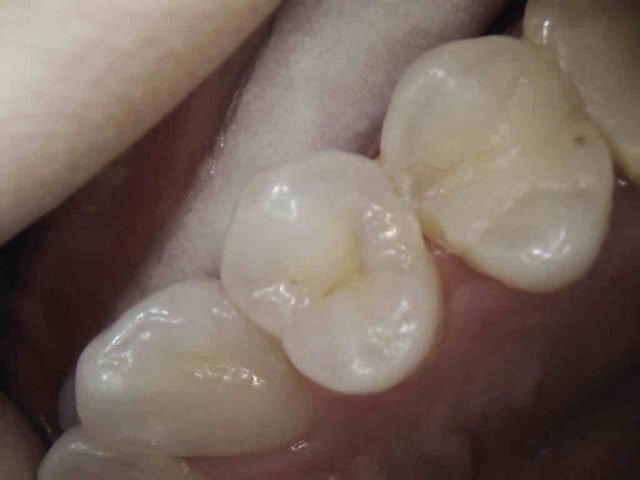

Patient 3: Tooth #12

This is a tough one for clinicians to believe, but the distal of #12 does, in fact, have caries! It appears less obvious and short of the DEJ. The photo mid-prep shows otherwise. Premolars, especially, are frail to begin with. Keeping any and all restorations conservative is the name of the game.